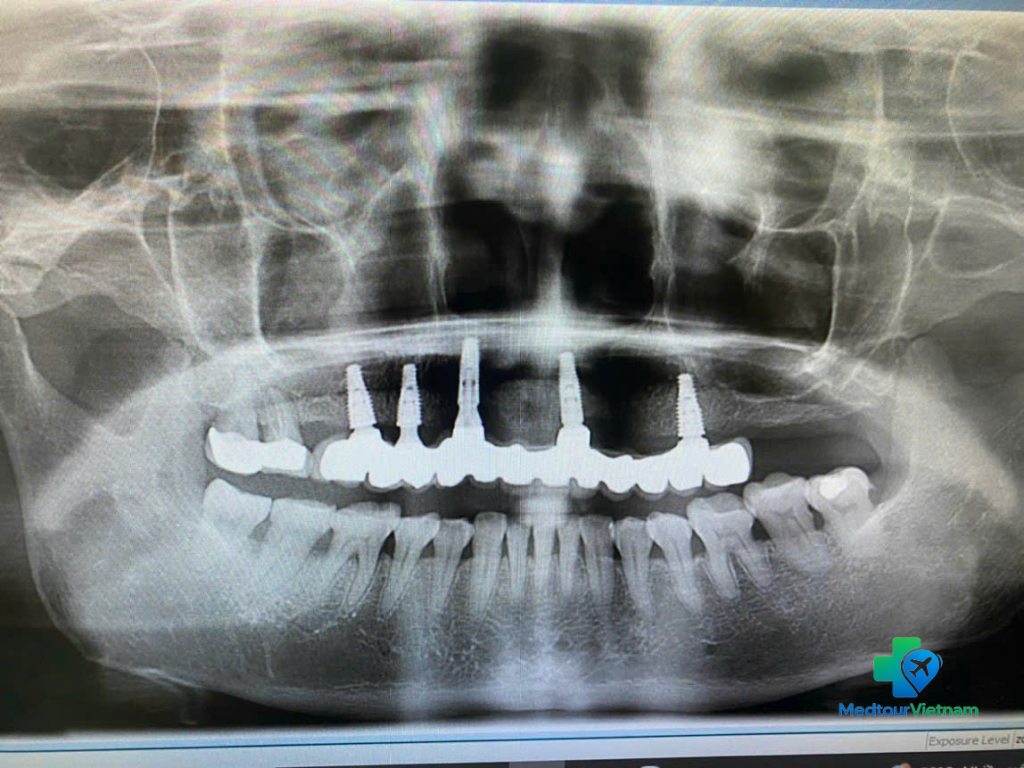

Panoramic X-ray used to assess bone structure and plan full mouth dental implants in Vietnam

Step 2: Surgery (Day 2–4)

Local anesthesia or sedation

Implant placement into the jawbone

Temporary crown or healing cap

Placement of dental implant posts in the upper jaw during full mouth restoration